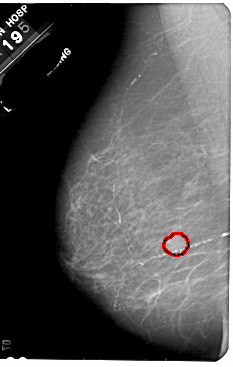

A_1836_1.LEFT_CC

LEFT_CC LINES 5491 PIXELS_PER_LINE 3361 BITS_PER_PIXEL 12 RESOLUTION 43.5 OVERLAY

FILE: A_1836_1.LEFT_CC.OVERLAY

TOTAL_ABNORMALITIES 1

ABNORMALITY 1

LESION_TYPE MASS SHAPE OVAL MARGINS OBSCURED

ASSESSMENT 3

SUBTLETY 5

PATHOLOGY BENIGN

TOTAL_OUTLINES 1

BOUNDARY